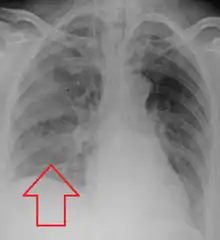

Aspiration pneumonia is typically diagnosed by a combination of clinical circumstances (people with risk factors for aspiration) and radiologic findings (an infiltrate in the proper location).[1] A chest x-ray is typically performed in cases where any pneumonia is suspected, including aspiration pneumonia.[18] Findings on chest x-ray supportive of aspiration pneumonia include localized consolidation depending on the patient's position when the aspiration occurred.[19] For example, people that are supine when they aspirate often develop consolidation in the right lower lobe of the lung.[19] Sputum cultures are not used for diagnosing aspiration pneumonia because of the high risk of contamination.[20] Clinical symptoms may also increase suspicion of aspiration pneumonia, including new difficulty breathing and fever after an aspiration event.[6] Likewise, physical exam findings such as altered breath sounds heard in the affected lung fields may also be suggestive of aspiration pneumonia.[6] Some cases of aspiration pneumonia are caused by aspiration of food particles or other particulate substances like pill fragments; these can be diagnosed by pathologists on lung biopsy specimens.[21]